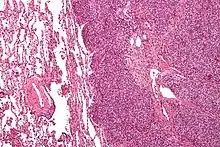

يعتمد التشخيص في الأساس على نتائج علم الأنسجة والكيمياء النسيجية المناعية وعلم الأمراض الجزيئي.

ساركومة يوينغ هو ورم من الخلايا الصغيرة الزرقاء المستديرة التي عادة ما تكون ذات سيتوبلازم نقي باستخدام صبغة الهيماتوكسيلين والإيوسين نتيجة وجود الجليكوجين. يمكن إيضاح وجود الجليكوجين بالنتيجة الإيجابية لصبغة PAS والنتيجة السلبية لصبغة دياستاز PAS. والملون المناعي المميز هو CD99، والذي يحدد غشاء الخلية بشكل كبير. يتم إثبات النتائج المورفولوجية والمناعية مع انتقال الكروموسومات الذي يحدث عادة. أكثر التكرارات شيوعًا التي تظهر في حوالي 90٪ من حالات ساركوما إوينغ هي الانتقال (11؛ 22) (q24؛ q12)،[11][12] الذي يولد عامل النسخ الشاذ من خلال دمج جين EWSR1 مع الجين FLI1.[13]

التشخيص التفريقي المَرَضي هو مجموعات الأورام ذات الخلايا الصغيرة الزرقاء المستديرة، والتي تشمل سرطان الغدد الليمفاوية والساركومة العضلية المخططة السنخية والأورام الصلدة (من النسيج الليفي) وغيرهم.